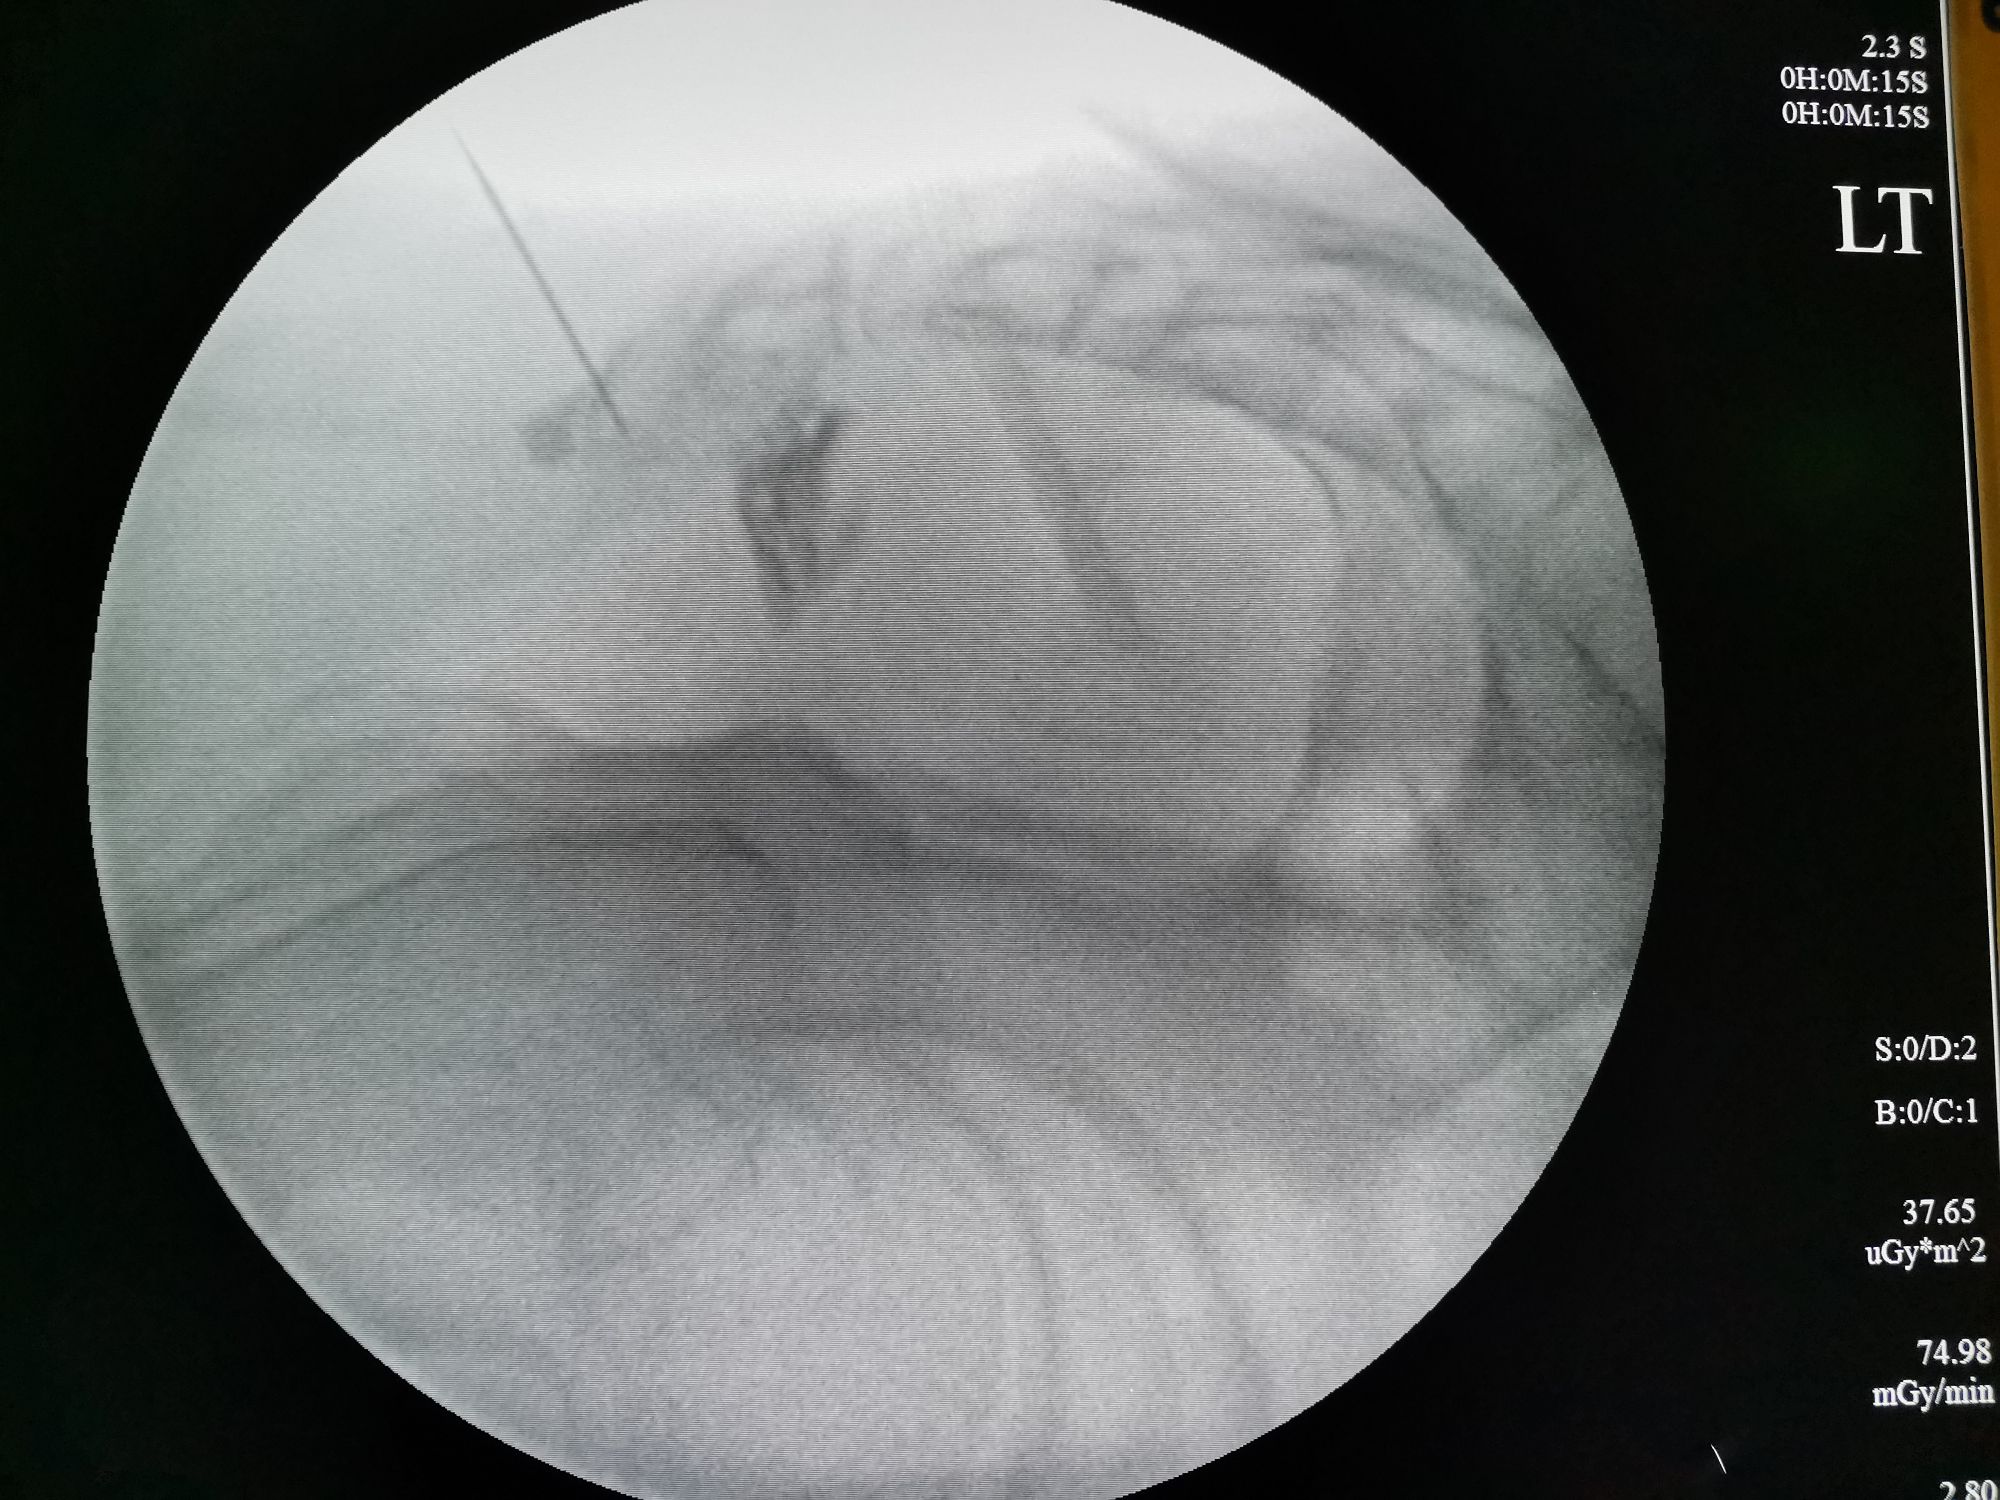

(该患者行奇神经节脉冲射频治疗,G臂定位显示穿刺位置准确,治疗效果能够最大化)